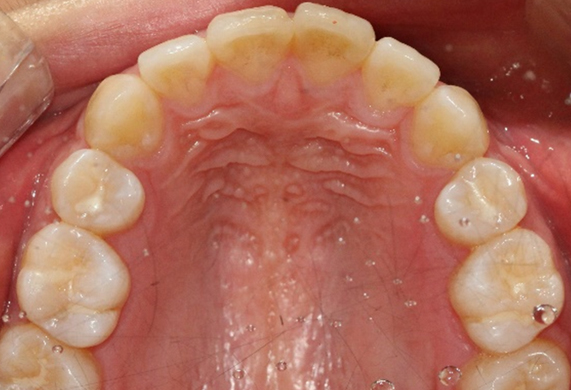

매복치 교정 CASE

-